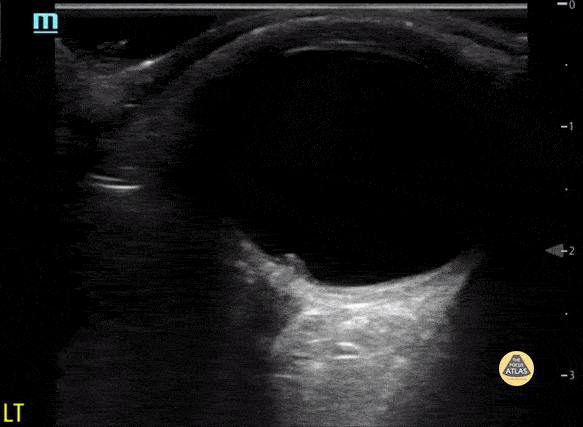

Optic disc elevation representing papilledema Contributor: Maher M. Abulfaraj, MD, @mahermabulfaraj

https://www.thepocusatlas.com/pedsorbital